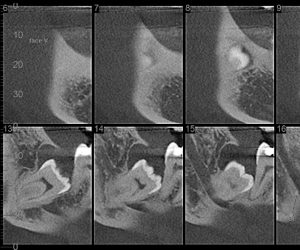

Cisto junto à coroa de um dente do siso retido/incluso

São os terceiros molares, os últimos dentes a nascer, geralmente entre os 17 e 25 anos.